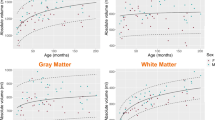

On T1-weighted 3.0T MRI, layers could be visualized at 14 weeks GA and appeared clearer after 18 weeks GA. On 7.0T MRI, four zones could be recognized at 14 weeks GA. During 15–22 weeks GA, when laminar organization appeared typical, seven layers including the periventricular zone and external capsule fibers could be differentiated, which corresponded to seven zones in histological stained sections. At 23–28 weeks GA, laminar organization appeared less typical, and borderlines among them appeared obscured. After 30 weeks GA, it disappeared and turned into mature-like structures. The developing lamination appeared the most distinguishable at the parieto-occipital part of brain and peripheral regions of the hippocampus. The migrating thalamocortical afferents were probably delineated as a high signal layer located at the lower, middle, and upper part of the subplate zone at 16–28 weeks GA on T1-weighted 3.0T MRI.

T1-weighted 3.0T MRI and T2-weighted 7.0T MRI can well demonstrate the laminar organization. Development of the lamination follows a specific spatio-temporal regularity, and postmortem MRI of the parieto-occipital part of brain obtained with 3.0T or 7.0T is an effective way to show developmental changes.

Developmental changes of laminar organization of the fetal cerebrum

On postmortem MRI, the lamination was described as layers with varying signal intensities. Changes related to GA could be revealed by layers’ appearance or disappearance, thickness, signal intensities, and borderlines.

Comparing images of different magnetic strength and scanning positions, it was found that the laminar organization was particularly clearer at the peripheral regions of the hippocampus and parieto-occipital part of brain.

In this study, it was found that 15–22 weeks GA was the period when laminar organization typically appeared, when the cerebral wall consisted of seven zones, and most of them could be clearly differentiated during this stage on the 3.0T or 7.0T postmortem MRIs. During 23–28 weeks GA, laminar organization appeared less typical with borderlines among them obscured. After 30 weeks GA, it disappeared and turned into mature-like structures. These results are consistent with previous findings from histological slides and T1-weighted images [2, 3].

In summary, T1-weighted 3.0T MRI and T2-weighted 7.0T MRI can well delineate the lamination. The development of laminar organization of the fetal cerebrum, which is typical at 15–22 weeks GA at the parieto-occipital lobe and peripheral regions of hippocampus on postmortem MRI, follows a specific spatio-temporal regularity. Postmortem MRI, which is free from the limitations of that of in vivo fetal MRI, can more clearly describe the laminar organization, and it can also demonstrate changes of signal intensities in the subplate zone, which are probably the migrating thalamocortical afferents.